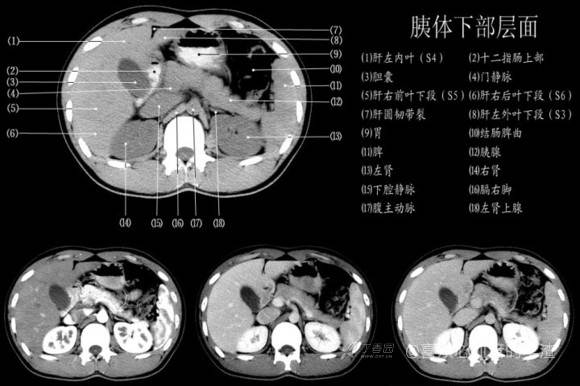

其实你离掌握上腹部 CT 影像只有一套高清实用图谱的距离,下面把我最喜欢的这本图谱分享给大家,为了方便阅读,我加了中文标识。后面附赠几张血管相对位置解剖关系图片,帮助大家理解(文中多图,建议在 wifi 环境下查看)。